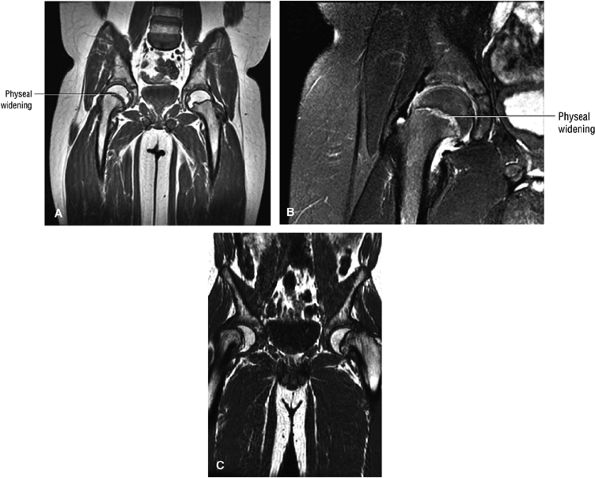

FIGURE 3.99 ● SCFE. (A, B) The femoral epiphysis is displaced posteriorly, medially, and inferiorly relative to the neck. There is widening of the physis with associated joint effusion. There is a relative decrease in the height of the epiphysis (similar to changes seen on conventional radiographs) and loss of intersection of the epiphysis by the lateral cortical (long axis) line of the femoral neck. The subsequent remodeling of the femoral neck creates a Herndon bump directly lateral to the physeal scar, similar to the location of the dysplastic femoral bump in FAI. (A) Coronal T1-weighted image. (B) Coronal FS PD FSE image. (C) A separate case showing a more severe Salter-Harris type I fracture contributing to varus hip deformity. Coronal T1-weighted image.